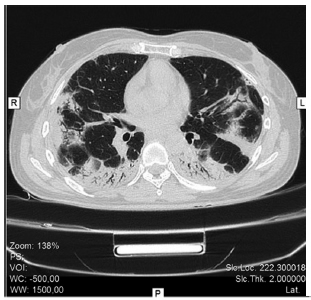

Los resultados iniciales de laboratorio mostraron ligera leucocitosis a predominio neutrofílico (11100/ mm3 Neutrófilos 68%) aumento de reactantes de fase aguda, (ESD 15 mm/h y PCR de 6.4 mg/l) y de enzimas musculares (GOT 166 U/L, CK 4155 U/L, Aldolasa 38.5 U/L). El examen funcional respiratorio mostró un patrón restrictivo con una CVF 1.34 L (41%), FEV1 1.26L (47%), disminución de volumen alveolar 2.19 L (47%) y una DLCO 32%. La tomografía de tórax evidenció compromiso difuso del parénquima pulmonar con mayor afectación de lóbulos inferiores, caracterizado por imágenes en vidrio esmerilado, de distribución subpleural y parcheada, con áreas de mayor compromiso alveolar con broncograma aéreo; se observan también aisladas bronquiectasias. (Figura 1)

Inició tratamiento inmunosupresor con pulsos metilprednisolona y ciclofosfamida. La paciente evolución en forma favorable, con disminución de los infiltrados pulmonares y parámetros inflamatorios. (Figura 2)